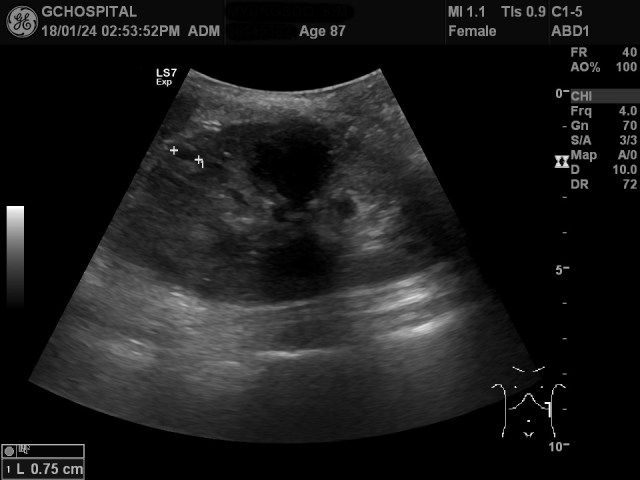

호홉을 조절해가면서 늑골에 의해 발생하는 음영을 피해 좌측신장을 확인하면서 몇 개의 작은 단순낭종을 발견했고, 위 영상은 그 중 윗부분에 존재했던 직경 8미리 정도의 낭종을 표시한 것입니다.

이러한 작은 단순낭종이 아래쪽에도 더 있을까 확인해보려 했지만, 좌측 신장이 흉곽 안에 들어있고, 환자분이 고령에 굉장히 깡마른 상태여서 시야가 잘 확보되지 않았습니다. 위 영상에서도 앞서와 비슷한 1센티미터 이하의 단순낭종이 신장 피막 바깥쪽으로 튀어나온 것이 보이지만, 이 외에도 좀 애매하게 안보이는 낭종들이 보여서 선형탐촉자를 갈비뼈 사이로 위치해서 더 확인해봤습니다.